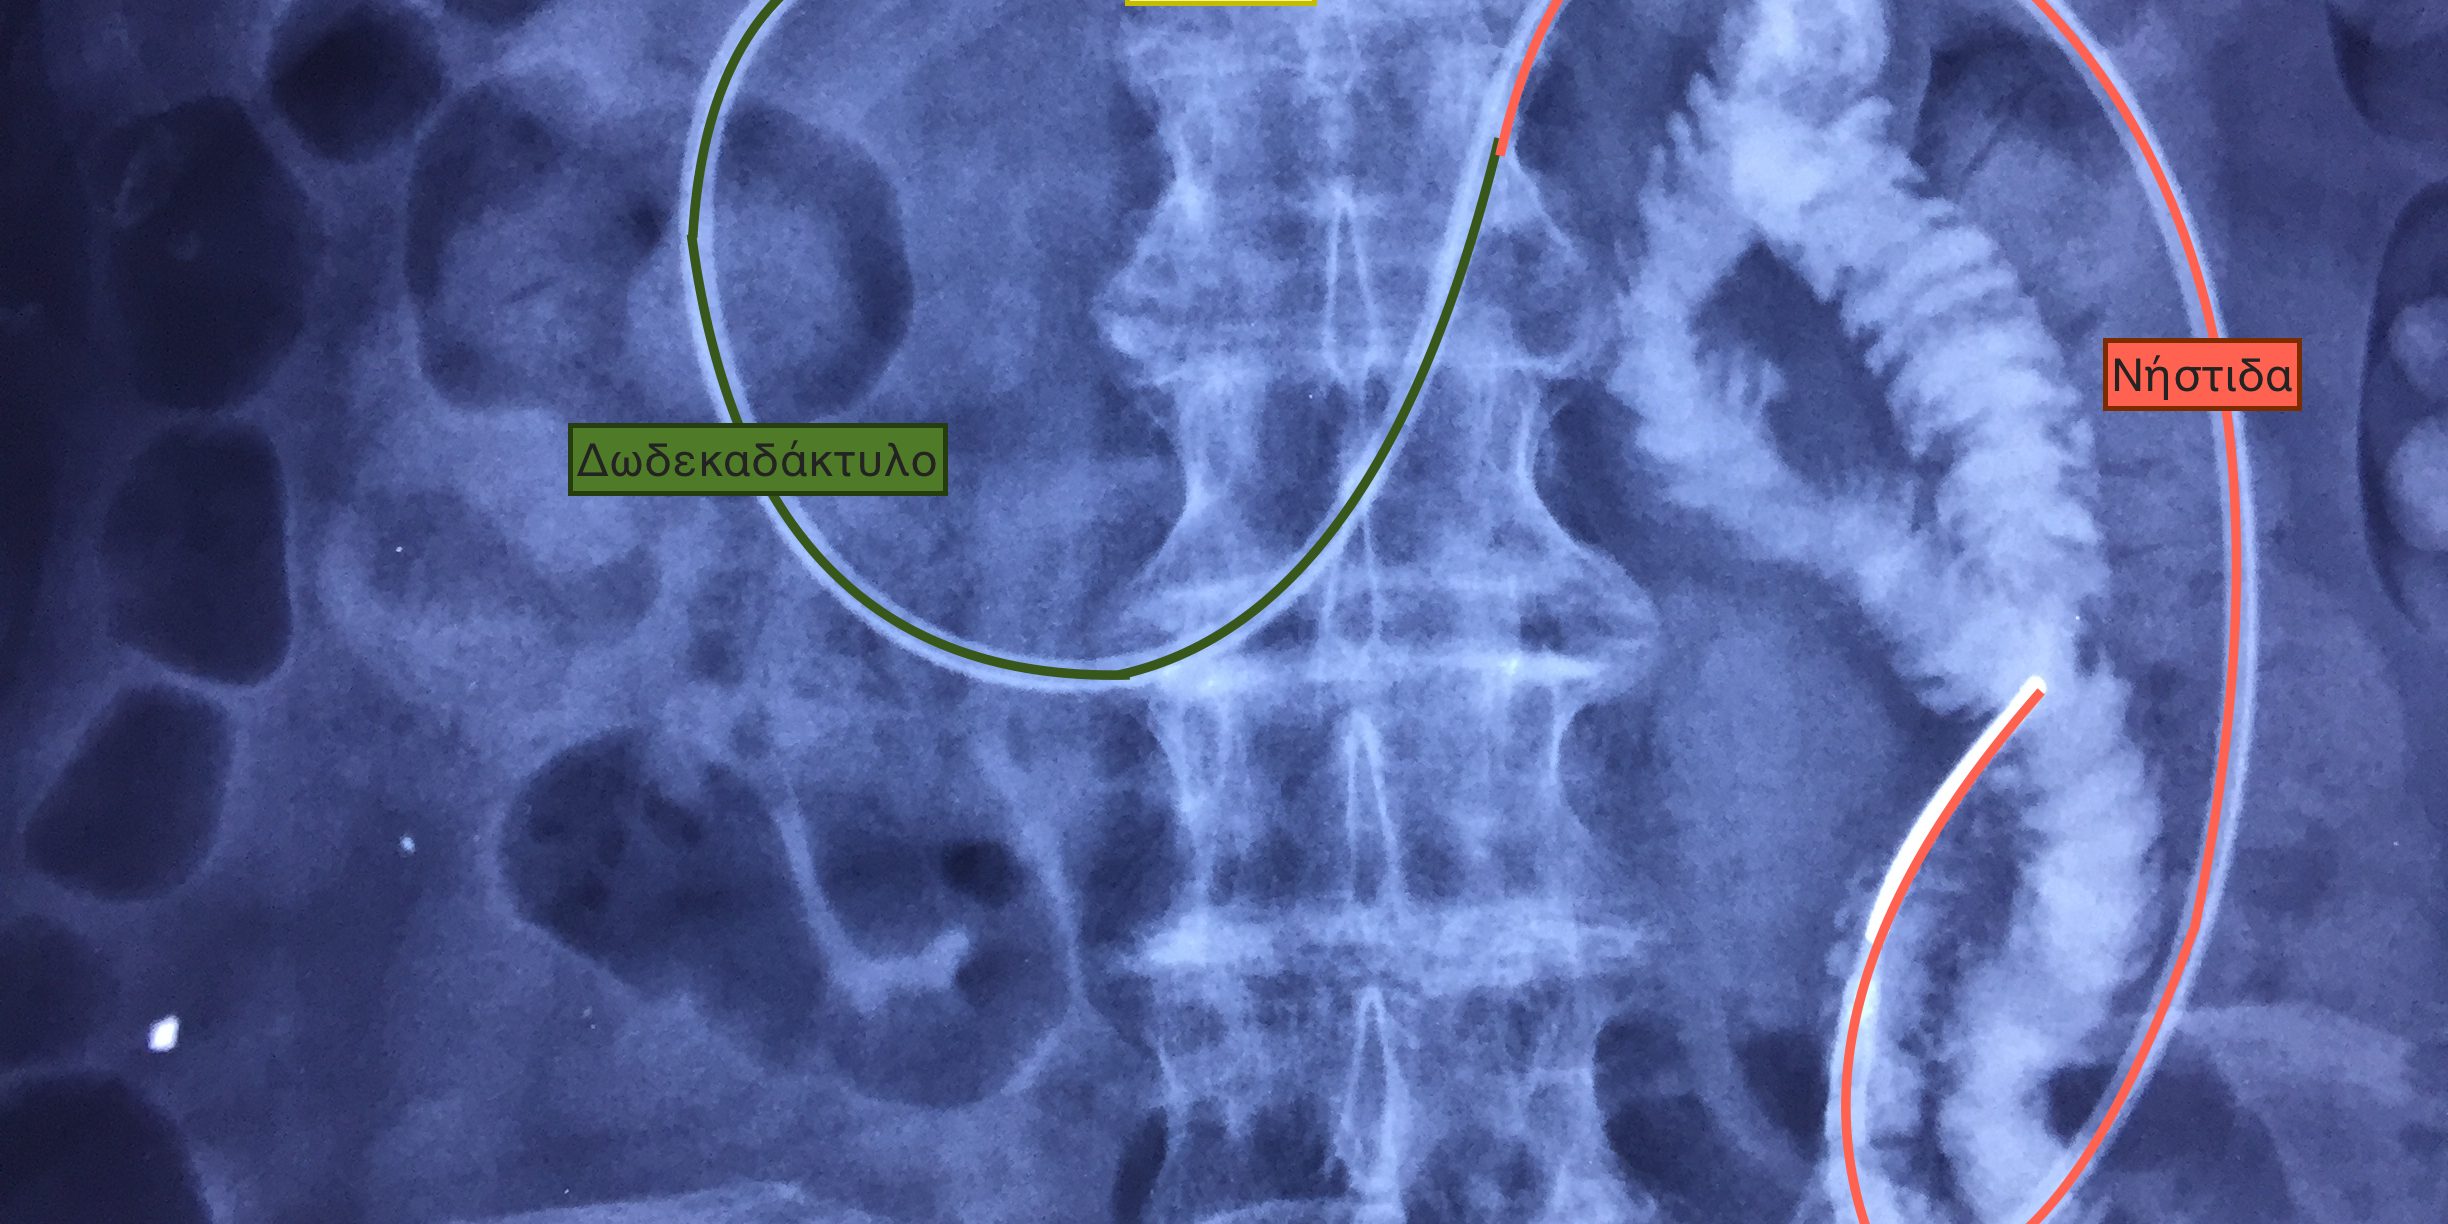

Δύο περιπτώσεις ενδοσκοπικής επανατοποθέτησης γαστρονηστιδικών σωλήνων, σε ηλικιωμένους ασθενείς που είχαν απλές γαστροστομιες και κινδύνευαν από επανειλημμένες εισροφήσεις τροφών, οι οποίες ανέβαιναν με αναγωγές προς το λαιμό και εισχωρούσαν στους πνεύμονες.

Η πρώτη περίπτωση αφορά άνδρα ηλικίας 95 ετών. Τα τελευταία 6 χρόνια σιτίζεται με γαστρονηστιδικό σωλήνα και δεν έχει κανένα αναπνευστικό πρόβλημα.

Η δεύτερη περίπτωση είναι γυναίκα 74 ετών. Τα τελευταία 2,5 χρόνια σιτίζεται με γαστρονηστιδικό καθετήρα, χωρίς προβλήματα πλέον με εισροφήσεις υγρών.